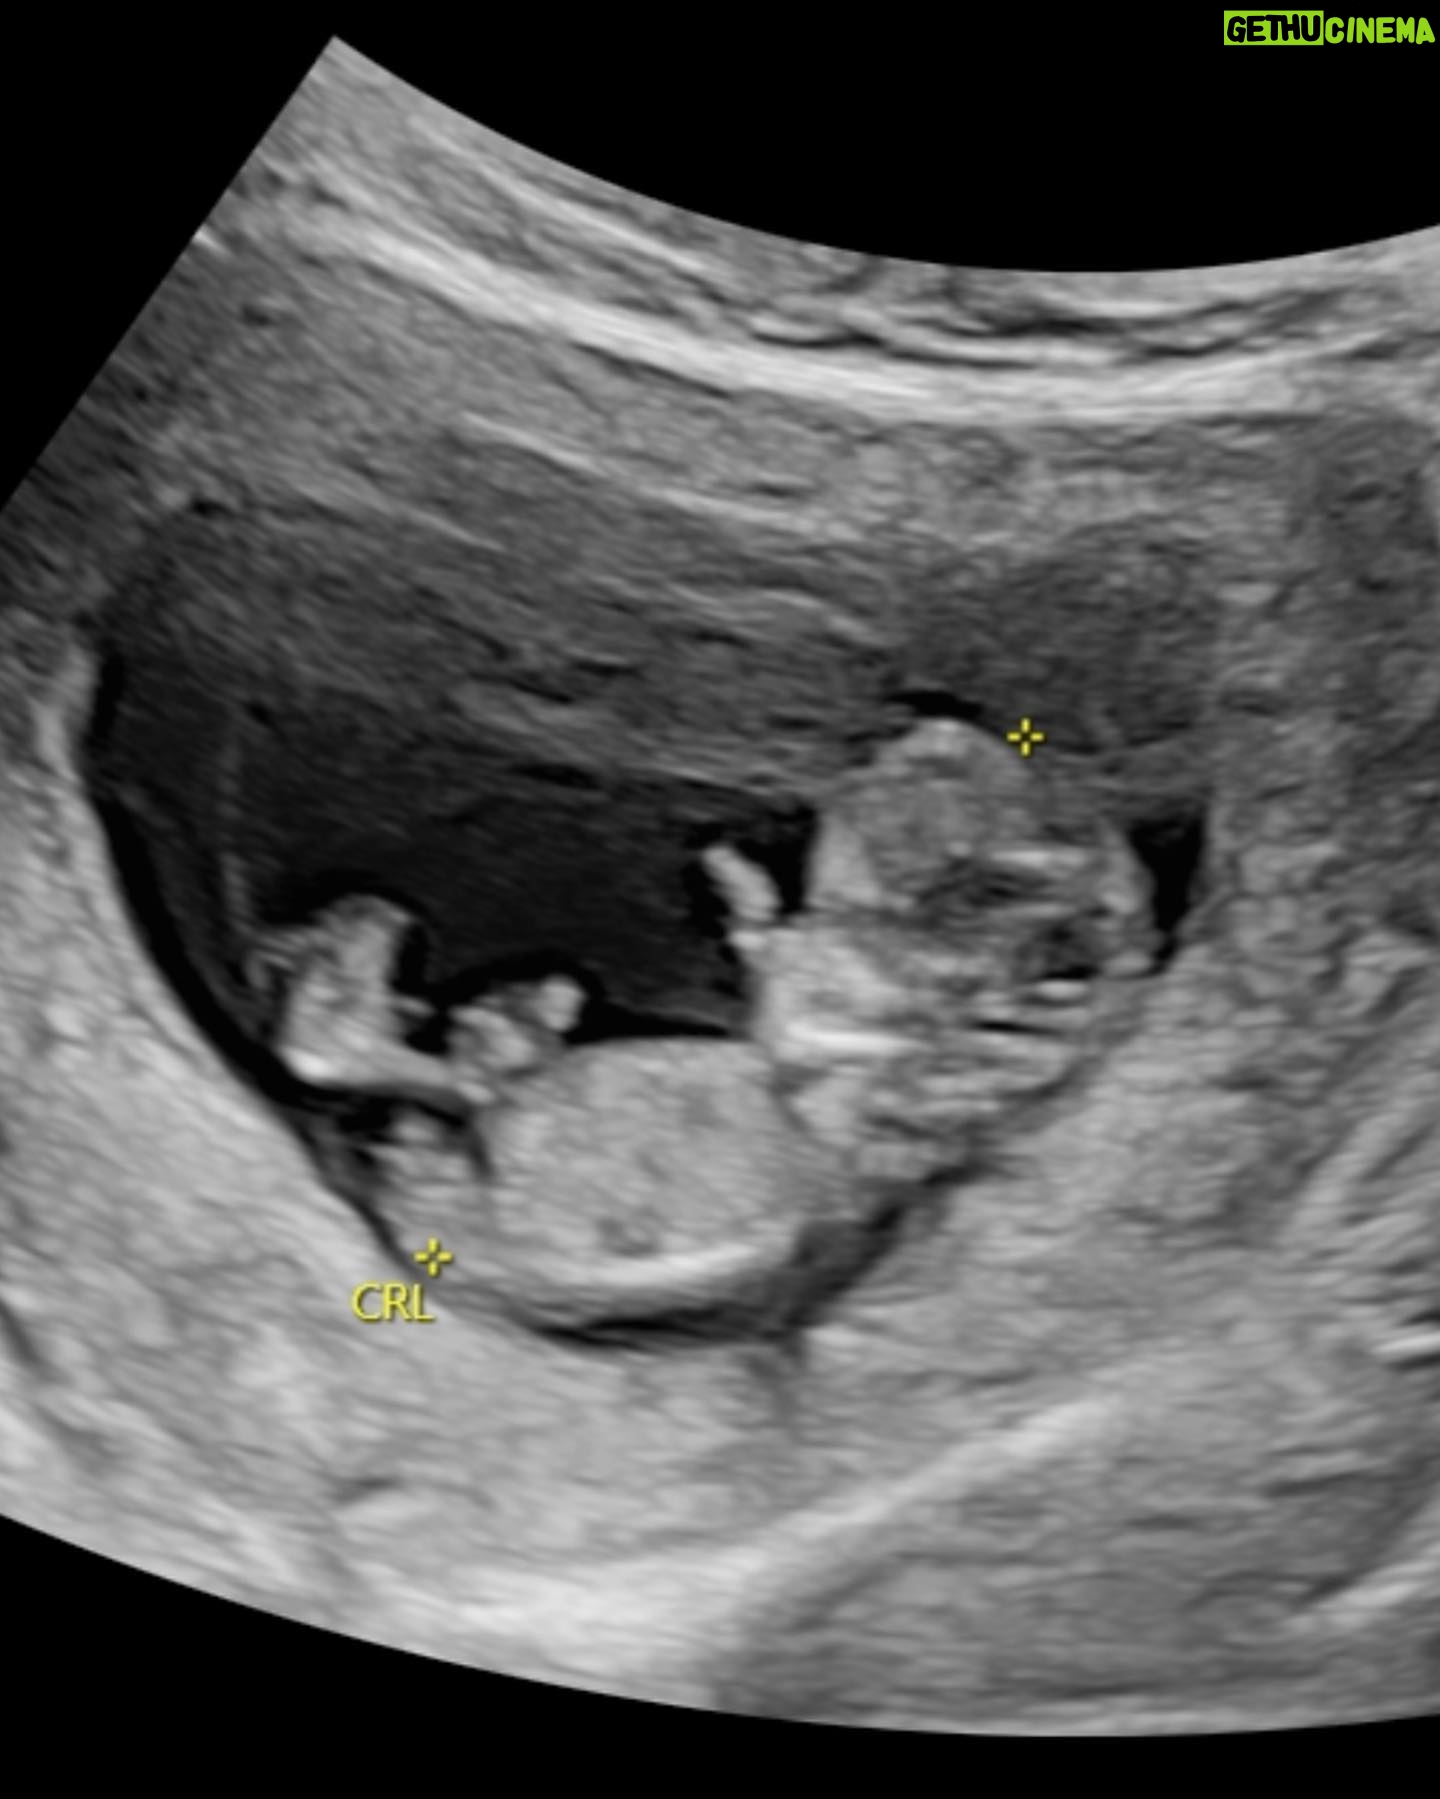

115.8K Likes – Liu Kuan-ting Instagram

Caption : 終於可以跟大家分享我們的新作品: 小太陽☀️👶🏻 還記得是3月《呼吸》演出的時候 每一場上場前,我們都會深深擁抱彼此 謝幕時看著對方的眼睛,盡在不言中 演出到第16場的時候 我看著眼前這個人 這個陪著我15年卻依然含淚看著我的人 突然發現自己不再恐懼婚姻和寶寶了 接著他偷偷準備了婚戒、一番試探 6月多驚喜又搞笑地讓我點頭了 7月初的時候因為生理痛痛到昏倒 還缺席了活動的我 發現要擁有一個寶寶也許真的是非常困難的事 8月時身體一直不太舒服、斷斷續續出血 他機警地載我去婦產科檢查 原以為的生病變成兩條線的大驚喜 寶寶沒讓我們等,非常順利地來報到了! 也終於了解為什麼大家總說要滿三個月 因為前期真的經歷了許多不穩定 去了幾次急診、流了一些眼淚 醫生說,健康的胚胎會自己留下來 不健康的胚胎打針也留不住,會自然淘汰 也請讓我在這裡跟和我一樣害怕過的女孩們說 不論發生任何事,都請妳不要責怪自己 等寶寶準備好了自然會來找我們的:) 謝謝經紀夥伴們、室友涵、好友們全力照顧 還有小舅舅的中藥、水藥,安胎又安心 連可怕的孕吐一次過後,一回診就緩解 平安健康滿三個多月的小太陽 終於可以來跟大家打招呼了👶🏻☀️! 多了一個新角色的我們 正在好好學習如何照顧自己、照顧她/他 這可能是我們接過最困難、也最甜蜜的新角色囉😚 真的很謝謝大家給的愛 未來也請多多指教☺️☺️🙏🏻 (另外,可能因為前期安胎的關係,我已腫成小胖子,肚子也好大⋯⋯金鐘獎紅毯請無條件誇我美🥹😆!!)Likes : 115826

115.8K Likes – Liu Kuan-ting Instagram

Caption : 終於可以跟大家分享我們的新作品: 小太陽☀️👶🏻 還記得是3月《呼吸》演出的時候 每一場上場前,我們都會深深擁抱彼此 謝幕時看著對方的眼睛,盡在不言中 演出到第16場的時候 我看著眼前這個人 這個陪著我15年卻依然含淚看著我的人 突然發現自己不再恐懼婚姻和寶寶了 接著他偷偷準備了婚戒、一番試探 6月多驚喜又搞笑地讓我點頭了 7月初的時候因為生理痛痛到昏倒 還缺席了活動的我 發現要擁有一個寶寶也許真的是非常困難的事 8月時身體一直不太舒服、斷斷續續出血 他機警地載我去婦產科檢查 原以為的生病變成兩條線的大驚喜 寶寶沒讓我們等,非常順利地來報到了! 也終於了解為什麼大家總說要滿三個月 因為前期真的經歷了許多不穩定 去了幾次急診、流了一些眼淚 醫生說,健康的胚胎會自己留下來 不健康的胚胎打針也留不住,會自然淘汰 也請讓我在這裡跟和我一樣害怕過的女孩們說 不論發生任何事,都請妳不要責怪自己 等寶寶準備好了自然會來找我們的:) 謝謝經紀夥伴們、室友涵、好友們全力照顧 還有小舅舅的中藥、水藥,安胎又安心 連可怕的孕吐一次過後,一回診就緩解 平安健康滿三個多月的小太陽 終於可以來跟大家打招呼了👶🏻☀️! 多了一個新角色的我們 正在好好學習如何照顧自己、照顧她/他 這可能是我們接過最困難、也最甜蜜的新角色囉😚 真的很謝謝大家給的愛 未來也請多多指教☺️☺️🙏🏻 (另外,可能因為前期安胎的關係,我已腫成小胖子,肚子也好大⋯⋯金鐘獎紅毯請無條件誇我美🥹😆!!)Likes : 115826

115.8K Likes – Liu Kuan-ting Instagram

Caption : 終於可以跟大家分享我們的新作品: 小太陽☀️👶🏻 還記得是3月《呼吸》演出的時候 每一場上場前,我們都會深深擁抱彼此 謝幕時看著對方的眼睛,盡在不言中 演出到第16場的時候 我看著眼前這個人 這個陪著我15年卻依然含淚看著我的人 突然發現自己不再恐懼婚姻和寶寶了 接著他偷偷準備了婚戒、一番試探 6月多驚喜又搞笑地讓我點頭了 7月初的時候因為生理痛痛到昏倒 還缺席了活動的我 發現要擁有一個寶寶也許真的是非常困難的事 8月時身體一直不太舒服、斷斷續續出血 他機警地載我去婦產科檢查 原以為的生病變成兩條線的大驚喜 寶寶沒讓我們等,非常順利地來報到了! 也終於了解為什麼大家總說要滿三個月 因為前期真的經歷了許多不穩定 去了幾次急診、流了一些眼淚 醫生說,健康的胚胎會自己留下來 不健康的胚胎打針也留不住,會自然淘汰 也請讓我在這裡跟和我一樣害怕過的女孩們說 不論發生任何事,都請妳不要責怪自己 等寶寶準備好了自然會來找我們的:) 謝謝經紀夥伴們、室友涵、好友們全力照顧 還有小舅舅的中藥、水藥,安胎又安心 連可怕的孕吐一次過後,一回診就緩解 平安健康滿三個多月的小太陽 終於可以來跟大家打招呼了👶🏻☀️! 多了一個新角色的我們 正在好好學習如何照顧自己、照顧她/他 這可能是我們接過最困難、也最甜蜜的新角色囉😚 真的很謝謝大家給的愛 未來也請多多指教☺️☺️🙏🏻 (另外,可能因為前期安胎的關係,我已腫成小胖子,肚子也好大⋯⋯金鐘獎紅毯請無條件誇我美🥹😆!!)Likes : 115826

115.8K Likes – Liu Kuan-ting Instagram

Caption : 終於可以跟大家分享我們的新作品: 小太陽☀️👶🏻 還記得是3月《呼吸》演出的時候 每一場上場前,我們都會深深擁抱彼此 謝幕時看著對方的眼睛,盡在不言中 演出到第16場的時候 我看著眼前這個人 這個陪著我15年卻依然含淚看著我的人 突然發現自己不再恐懼婚姻和寶寶了 接著他偷偷準備了婚戒、一番試探 6月多驚喜又搞笑地讓我點頭了 7月初的時候因為生理痛痛到昏倒 還缺席了活動的我 發現要擁有一個寶寶也許真的是非常困難的事 8月時身體一直不太舒服、斷斷續續出血 他機警地載我去婦產科檢查 原以為的生病變成兩條線的大驚喜 寶寶沒讓我們等,非常順利地來報到了! 也終於了解為什麼大家總說要滿三個月 因為前期真的經歷了許多不穩定 去了幾次急診、流了一些眼淚 醫生說,健康的胚胎會自己留下來 不健康的胚胎打針也留不住,會自然淘汰 也請讓我在這裡跟和我一樣害怕過的女孩們說 不論發生任何事,都請妳不要責怪自己 等寶寶準備好了自然會來找我們的:) 謝謝經紀夥伴們、室友涵、好友們全力照顧 還有小舅舅的中藥、水藥,安胎又安心 連可怕的孕吐一次過後,一回診就緩解 平安健康滿三個多月的小太陽 終於可以來跟大家打招呼了👶🏻☀️! 多了一個新角色的我們 正在好好學習如何照顧自己、照顧她/他 這可能是我們接過最困難、也最甜蜜的新角色囉😚 真的很謝謝大家給的愛 未來也請多多指教☺️☺️🙏🏻 (另外,可能因為前期安胎的關係,我已腫成小胖子,肚子也好大⋯⋯金鐘獎紅毯請無條件誇我美🥹😆!!)Likes : 115826

115.8K Likes – Liu Kuan-ting Instagram

Caption : 終於可以跟大家分享我們的新作品: 小太陽☀️👶🏻 還記得是3月《呼吸》演出的時候 每一場上場前,我們都會深深擁抱彼此 謝幕時看著對方的眼睛,盡在不言中 演出到第16場的時候 我看著眼前這個人 這個陪著我15年卻依然含淚看著我的人 突然發現自己不再恐懼婚姻和寶寶了 接著他偷偷準備了婚戒、一番試探 6月多驚喜又搞笑地讓我點頭了 7月初的時候因為生理痛痛到昏倒 還缺席了活動的我 發現要擁有一個寶寶也許真的是非常困難的事 8月時身體一直不太舒服、斷斷續續出血 他機警地載我去婦產科檢查 原以為的生病變成兩條線的大驚喜 寶寶沒讓我們等,非常順利地來報到了! 也終於了解為什麼大家總說要滿三個月 因為前期真的經歷了許多不穩定 去了幾次急診、流了一些眼淚 醫生說,健康的胚胎會自己留下來 不健康的胚胎打針也留不住,會自然淘汰 也請讓我在這裡跟和我一樣害怕過的女孩們說 不論發生任何事,都請妳不要責怪自己 等寶寶準備好了自然會來找我們的:) 謝謝經紀夥伴們、室友涵、好友們全力照顧 還有小舅舅的中藥、水藥,安胎又安心 連可怕的孕吐一次過後,一回診就緩解 平安健康滿三個多月的小太陽 終於可以來跟大家打招呼了👶🏻☀️! 多了一個新角色的我們 正在好好學習如何照顧自己、照顧她/他 這可能是我們接過最困難、也最甜蜜的新角色囉😚 真的很謝謝大家給的愛 未來也請多多指教☺️☺️🙏🏻 (另外,可能因為前期安胎的關係,我已腫成小胖子,肚子也好大⋯⋯金鐘獎紅毯請無條件誇我美🥹😆!!)Likes : 115826

115.8K Likes – Liu Kuan-ting Instagram

Caption : 終於可以跟大家分享我們的新作品: 小太陽☀️👶🏻 還記得是3月《呼吸》演出的時候 每一場上場前,我們都會深深擁抱彼此 謝幕時看著對方的眼睛,盡在不言中 演出到第16場的時候 我看著眼前這個人 這個陪著我15年卻依然含淚看著我的人 突然發現自己不再恐懼婚姻和寶寶了 接著他偷偷準備了婚戒、一番試探 6月多驚喜又搞笑地讓我點頭了 7月初的時候因為生理痛痛到昏倒 還缺席了活動的我 發現要擁有一個寶寶也許真的是非常困難的事 8月時身體一直不太舒服、斷斷續續出血 他機警地載我去婦產科檢查 原以為的生病變成兩條線的大驚喜 寶寶沒讓我們等,非常順利地來報到了! 也終於了解為什麼大家總說要滿三個月 因為前期真的經歷了許多不穩定 去了幾次急診、流了一些眼淚 醫生說,健康的胚胎會自己留下來 不健康的胚胎打針也留不住,會自然淘汰 也請讓我在這裡跟和我一樣害怕過的女孩們說 不論發生任何事,都請妳不要責怪自己 等寶寶準備好了自然會來找我們的:) 謝謝經紀夥伴們、室友涵、好友們全力照顧 還有小舅舅的中藥、水藥,安胎又安心 連可怕的孕吐一次過後,一回診就緩解 平安健康滿三個多月的小太陽 終於可以來跟大家打招呼了👶🏻☀️! 多了一個新角色的我們 正在好好學習如何照顧自己、照顧她/他 這可能是我們接過最困難、也最甜蜜的新角色囉😚 真的很謝謝大家給的愛 未來也請多多指教☺️☺️🙏🏻 (另外,可能因為前期安胎的關係,我已腫成小胖子,肚子也好大⋯⋯金鐘獎紅毯請無條件誇我美🥹😆!!)Likes : 115826